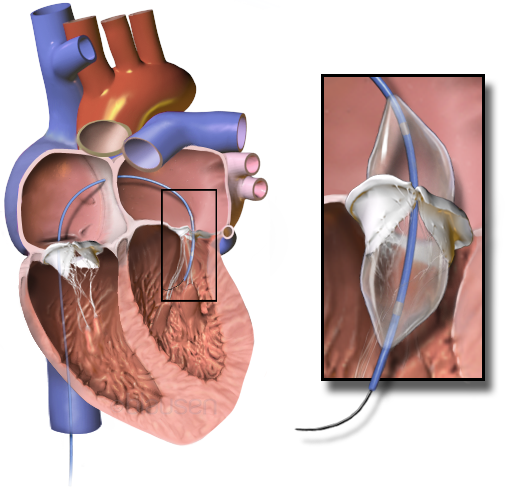

Treatment of aortic stenosis is valve replacement.

Treatment of aortic regurgitation is valve replacement once left ventricle dysfunction develops.

Treatment of aortic regurgitation is valve replacement.